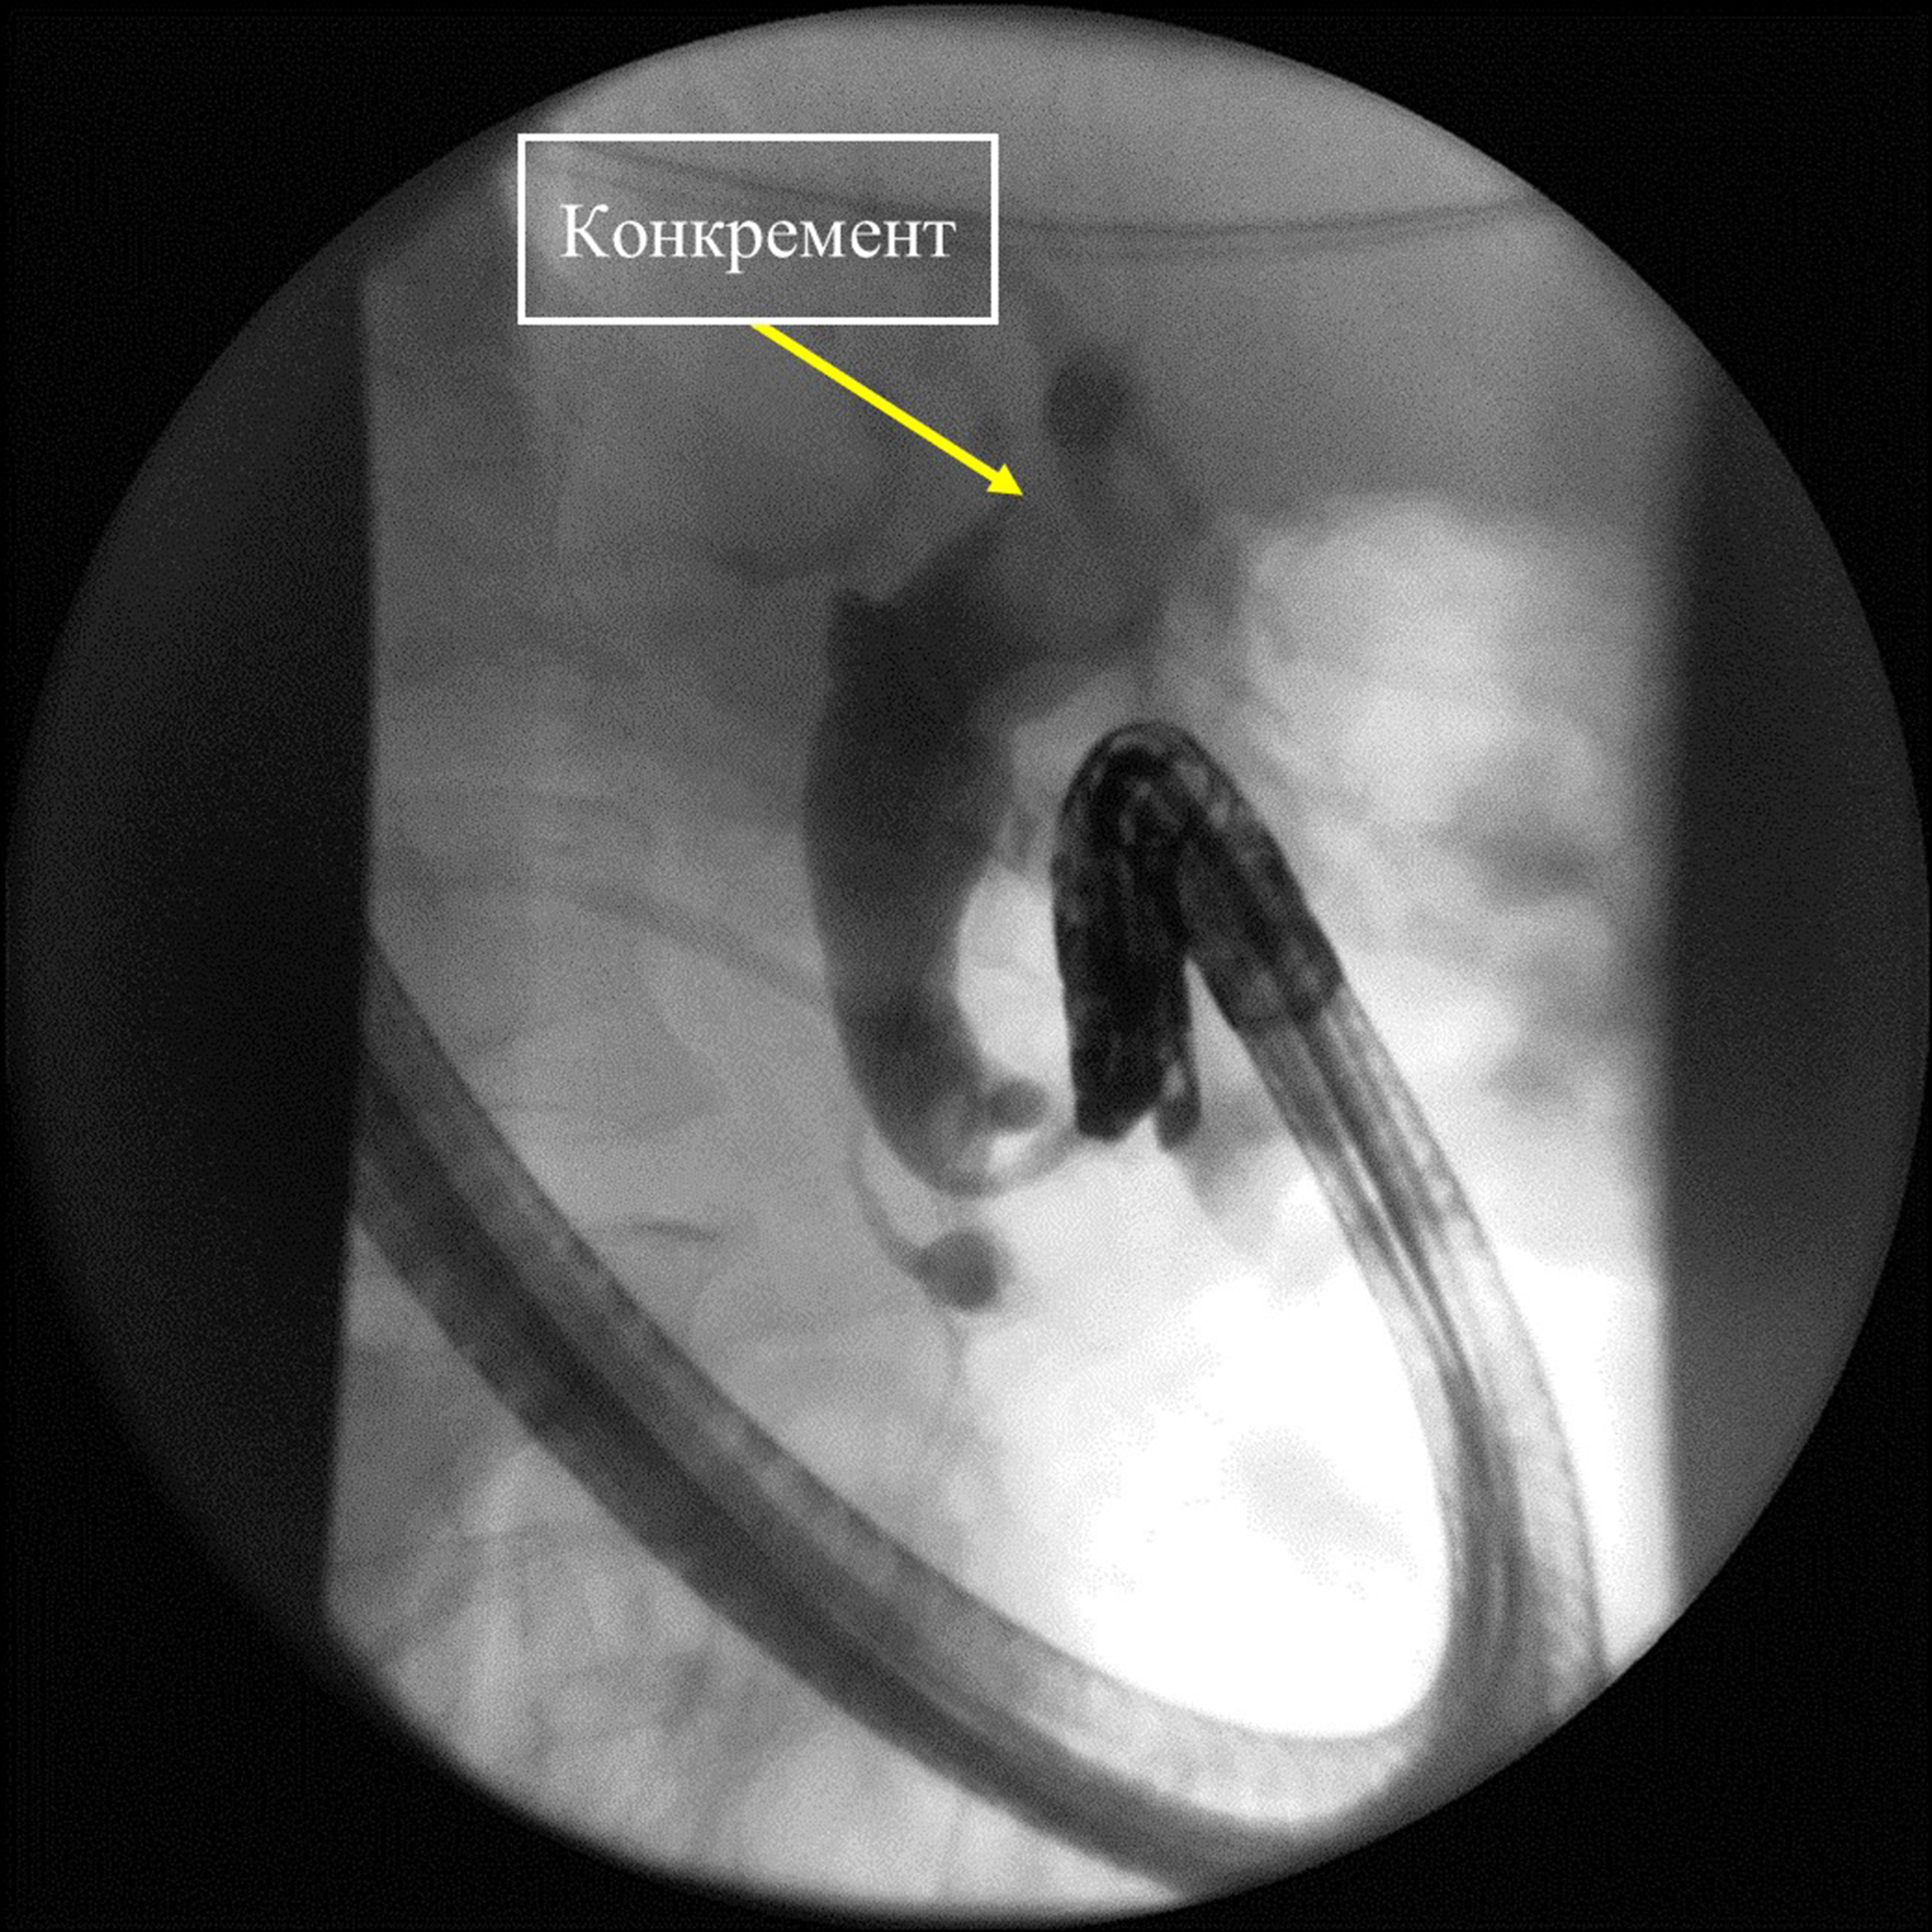

Представлено клиническое наблюдение пациента с желчнокаменной болезнью и так называемым трудным холедохолитиазом. Ввиду развившихся осложнений – механической желтухи и гнойного холангита, а также вследствие большого операционного риска от открытого оперативного вмешательства решено воздержаться. Попытки эндоскопической литэкстракции традиционными способами не увенчались успехом. Выполнены контактная электроимпульсная литотрипсия, литэкстракция. Это позволило устранить холедохолитиаз, восстановить проходимость желчных протоков, ликвидировать холангит и обеспечить возможность безопасного планового оперативного вмешательства по поводу хронического калькулезного холецистита.

Эндоскопическая ретроградная контактная электроимпульсная литотрипсия и литэкстракция